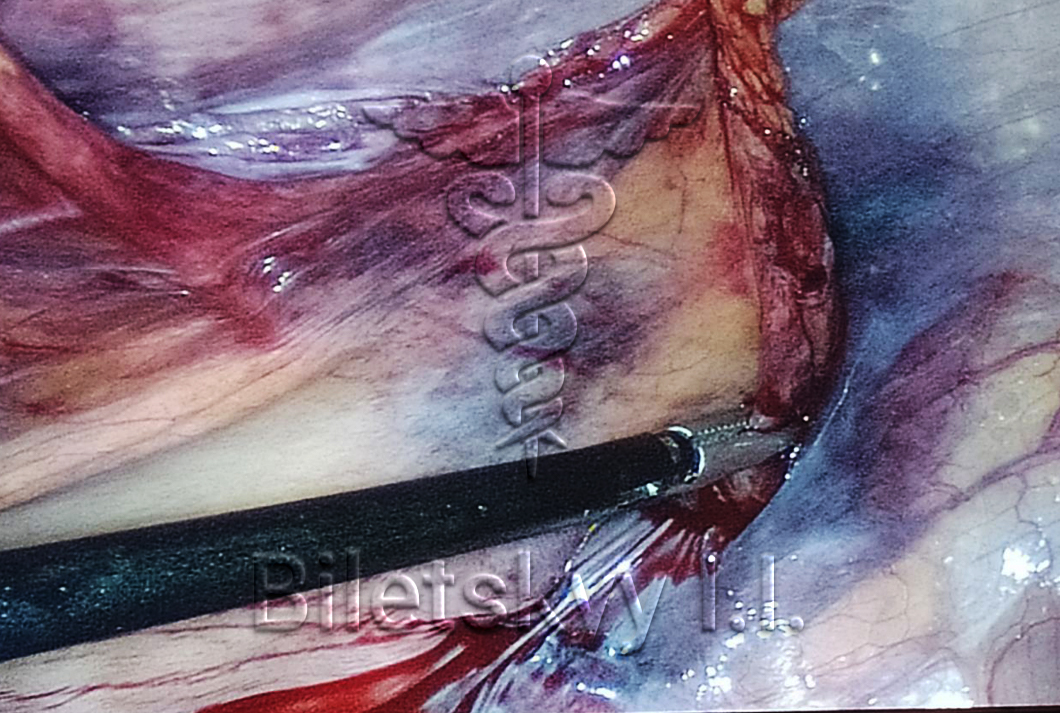

Спайкова хвороба очеревини

Під спайковою хворобою черевної порожнини часто мають на увазі збірне поняття, що позначає формування тяжів з сполучної тканини (спайки), що виникають після перенесених операцій, запальних захворювань, травм та інших процесів. В результаті формування спайок між очеревиною та органами черевної порожнини можуть розвиватися різні патології, що включають в себе механічну кишечну непрохідність, зміщення внутрішніх органів і т.д. Методи хірургічного лікування включають:

- Лапаротомію (розтин передньої брюшної стінки) з розсіченням спайок;

- Лапароскопічну операцію з розсіченням спайок.